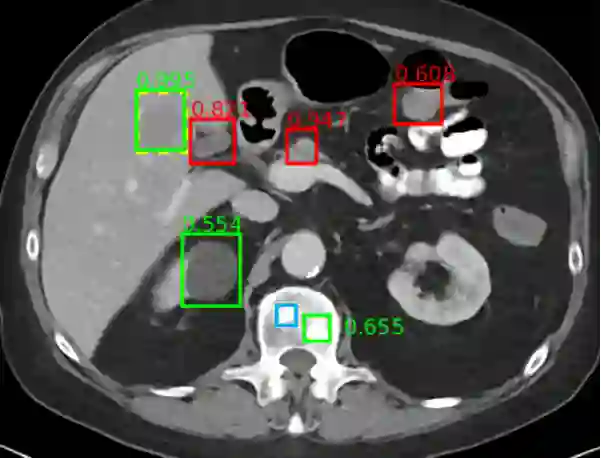

CT、MRI、超声、PET等影像常被用于腹部的临床决策。为了辅助临床决策,最近医学影像AI技术在腹部解剖结构分割、疾病自动检测和分类方面取得了不少进展,这主要得益于技术的进步和大型公共数据集(例如MICCAI数据十项全能和DeepLesion数据集)的促进作用。综述简要地回顾了腹部多器官分割病变检测分析机会性筛选opportunistic screening)这三个方面的研究。图6展示了腹部CT的通用病变检测结果示例。

6)腹部CT的通用病变检测。在此上腹部的轴向图像中,以高置信度正确检测(见绿色框)到肝脏病变(0.995),还正确检测到肾囊肿(0.554)和骨转移(0.655)。误报(见红色框)包括正常胰腺(0.947),胆囊(0.821)和肠(0.608)。遗漏了微妙的骨转移(见蓝色框)。